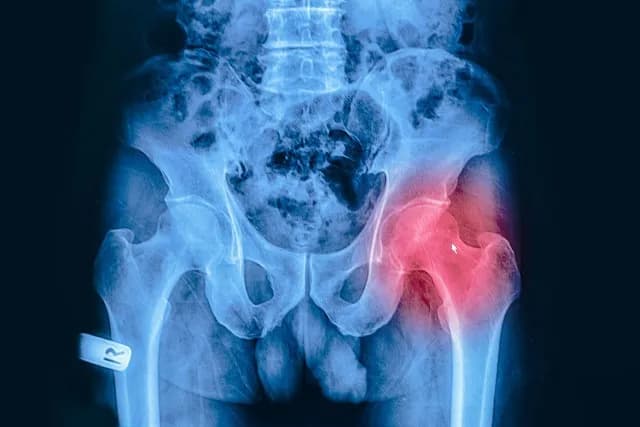

W diagnostyce chorób stawów kluczowe są różne badania obrazowe, które umożliwiają ocenę stanu stawów i wykrywanie zmian degeneracyjnych. Każda z metod ma swoje specyficzne zastosowanie oraz korzyści, co sprawia, że są one niezbędne w procesie diagnostycznym. Wśród najczęściej stosowanych technik znajdują się zdjęcia rentgenowskie, rezonans magnetyczny oraz tomografia komputerowa. Każda z tych metod dostarcza cennych informacji, które pomagają lekarzom w podejmowaniu decyzji dotyczących dalszego leczenia.

Zdjęcia rentgenowskie są podstawowym narzędziem diagnostycznym, które pozwala na ocenę struktury kości w stawach. Dzięki nim można wykryć zmiany, takie jak zwężenie przestrzeni stawowej czy obecność osteofitów. Rezonans magnetyczny (MRI) natomiast oferuje szczegółowe obrazowanie tkanek miękkich, co jest niezwykle pomocne w ocenie chrząstki, więzadeł i mięśni. Tomografia komputerowa (TK) dostarcza jeszcze bardziej szczegółowych informacji, szczególnie w przypadku skomplikowanych urazów stawów.

Zdjęcia rentgenowskie stawów są jedną z podstawowych metod diagnostycznych w ocenie chorób zwyrodnieniowych. X-ray pozwala na wykrycie istotnych zmian w strukturze stawów, takich jak zwężenie przestrzeni stawowej, co może wskazywać na postępującą degenerację. Dodatkowo, na zdjęciach rentgenowskich można zaobserwować obecność osteofitów, czyli wyrostków kostnych, które często pojawiają się w wyniku przewlekłego stanu zapalnego. Choć zdjęcia rentgenowskie są pomocne w ocenie stopnia zaawansowania choroby, mogą nie wykrywać wczesnych zmian, które są widoczne w bardziej zaawansowanych badaniach obrazowych.